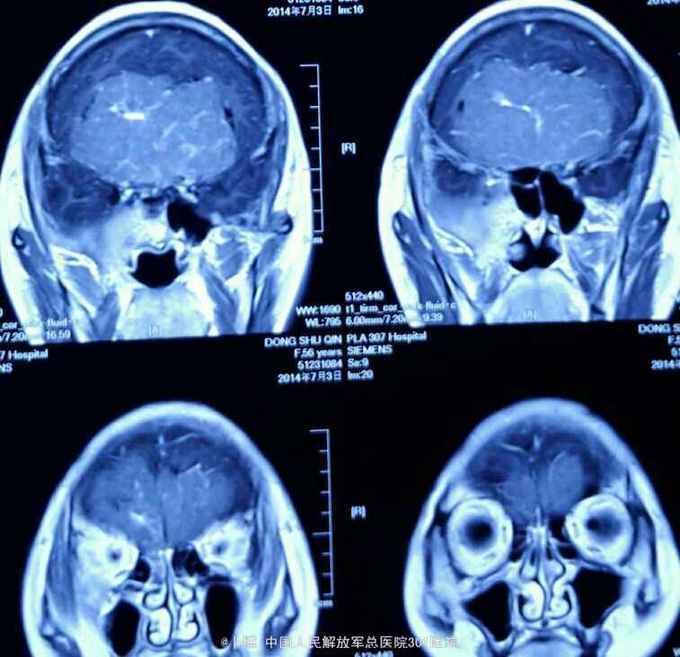

前颅窝底占位:脑膜瘤

脑膜瘤

头痛伴记忆力下降8个月。家属发现患者反应迟钝,记忆力下降。对人淡漠。

神清语利。定向力正常。计算力下降。双侧嗅觉丧失。视力下降,双侧0.5。眼底视乳头边界不清。眼球各方运动正常。余神经系统阴性。

前颅窝底占位:脑膜瘤。 手术入路:冠状切口,双侧额下入路肿瘤切除。